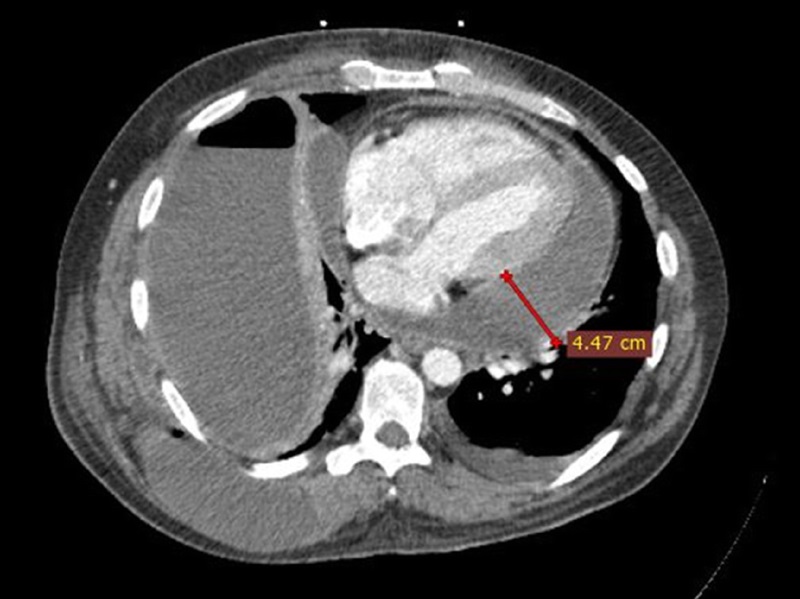

Pestrea et al. report a successfully treated case of an immunocompetent young Muay Thai fighter who developed purulent pericarditis and cardiac tamponade due to contiguous spread from an infected hydropneumothorax secondary to traumatic rib fracture. brnw.ch/21wRK97